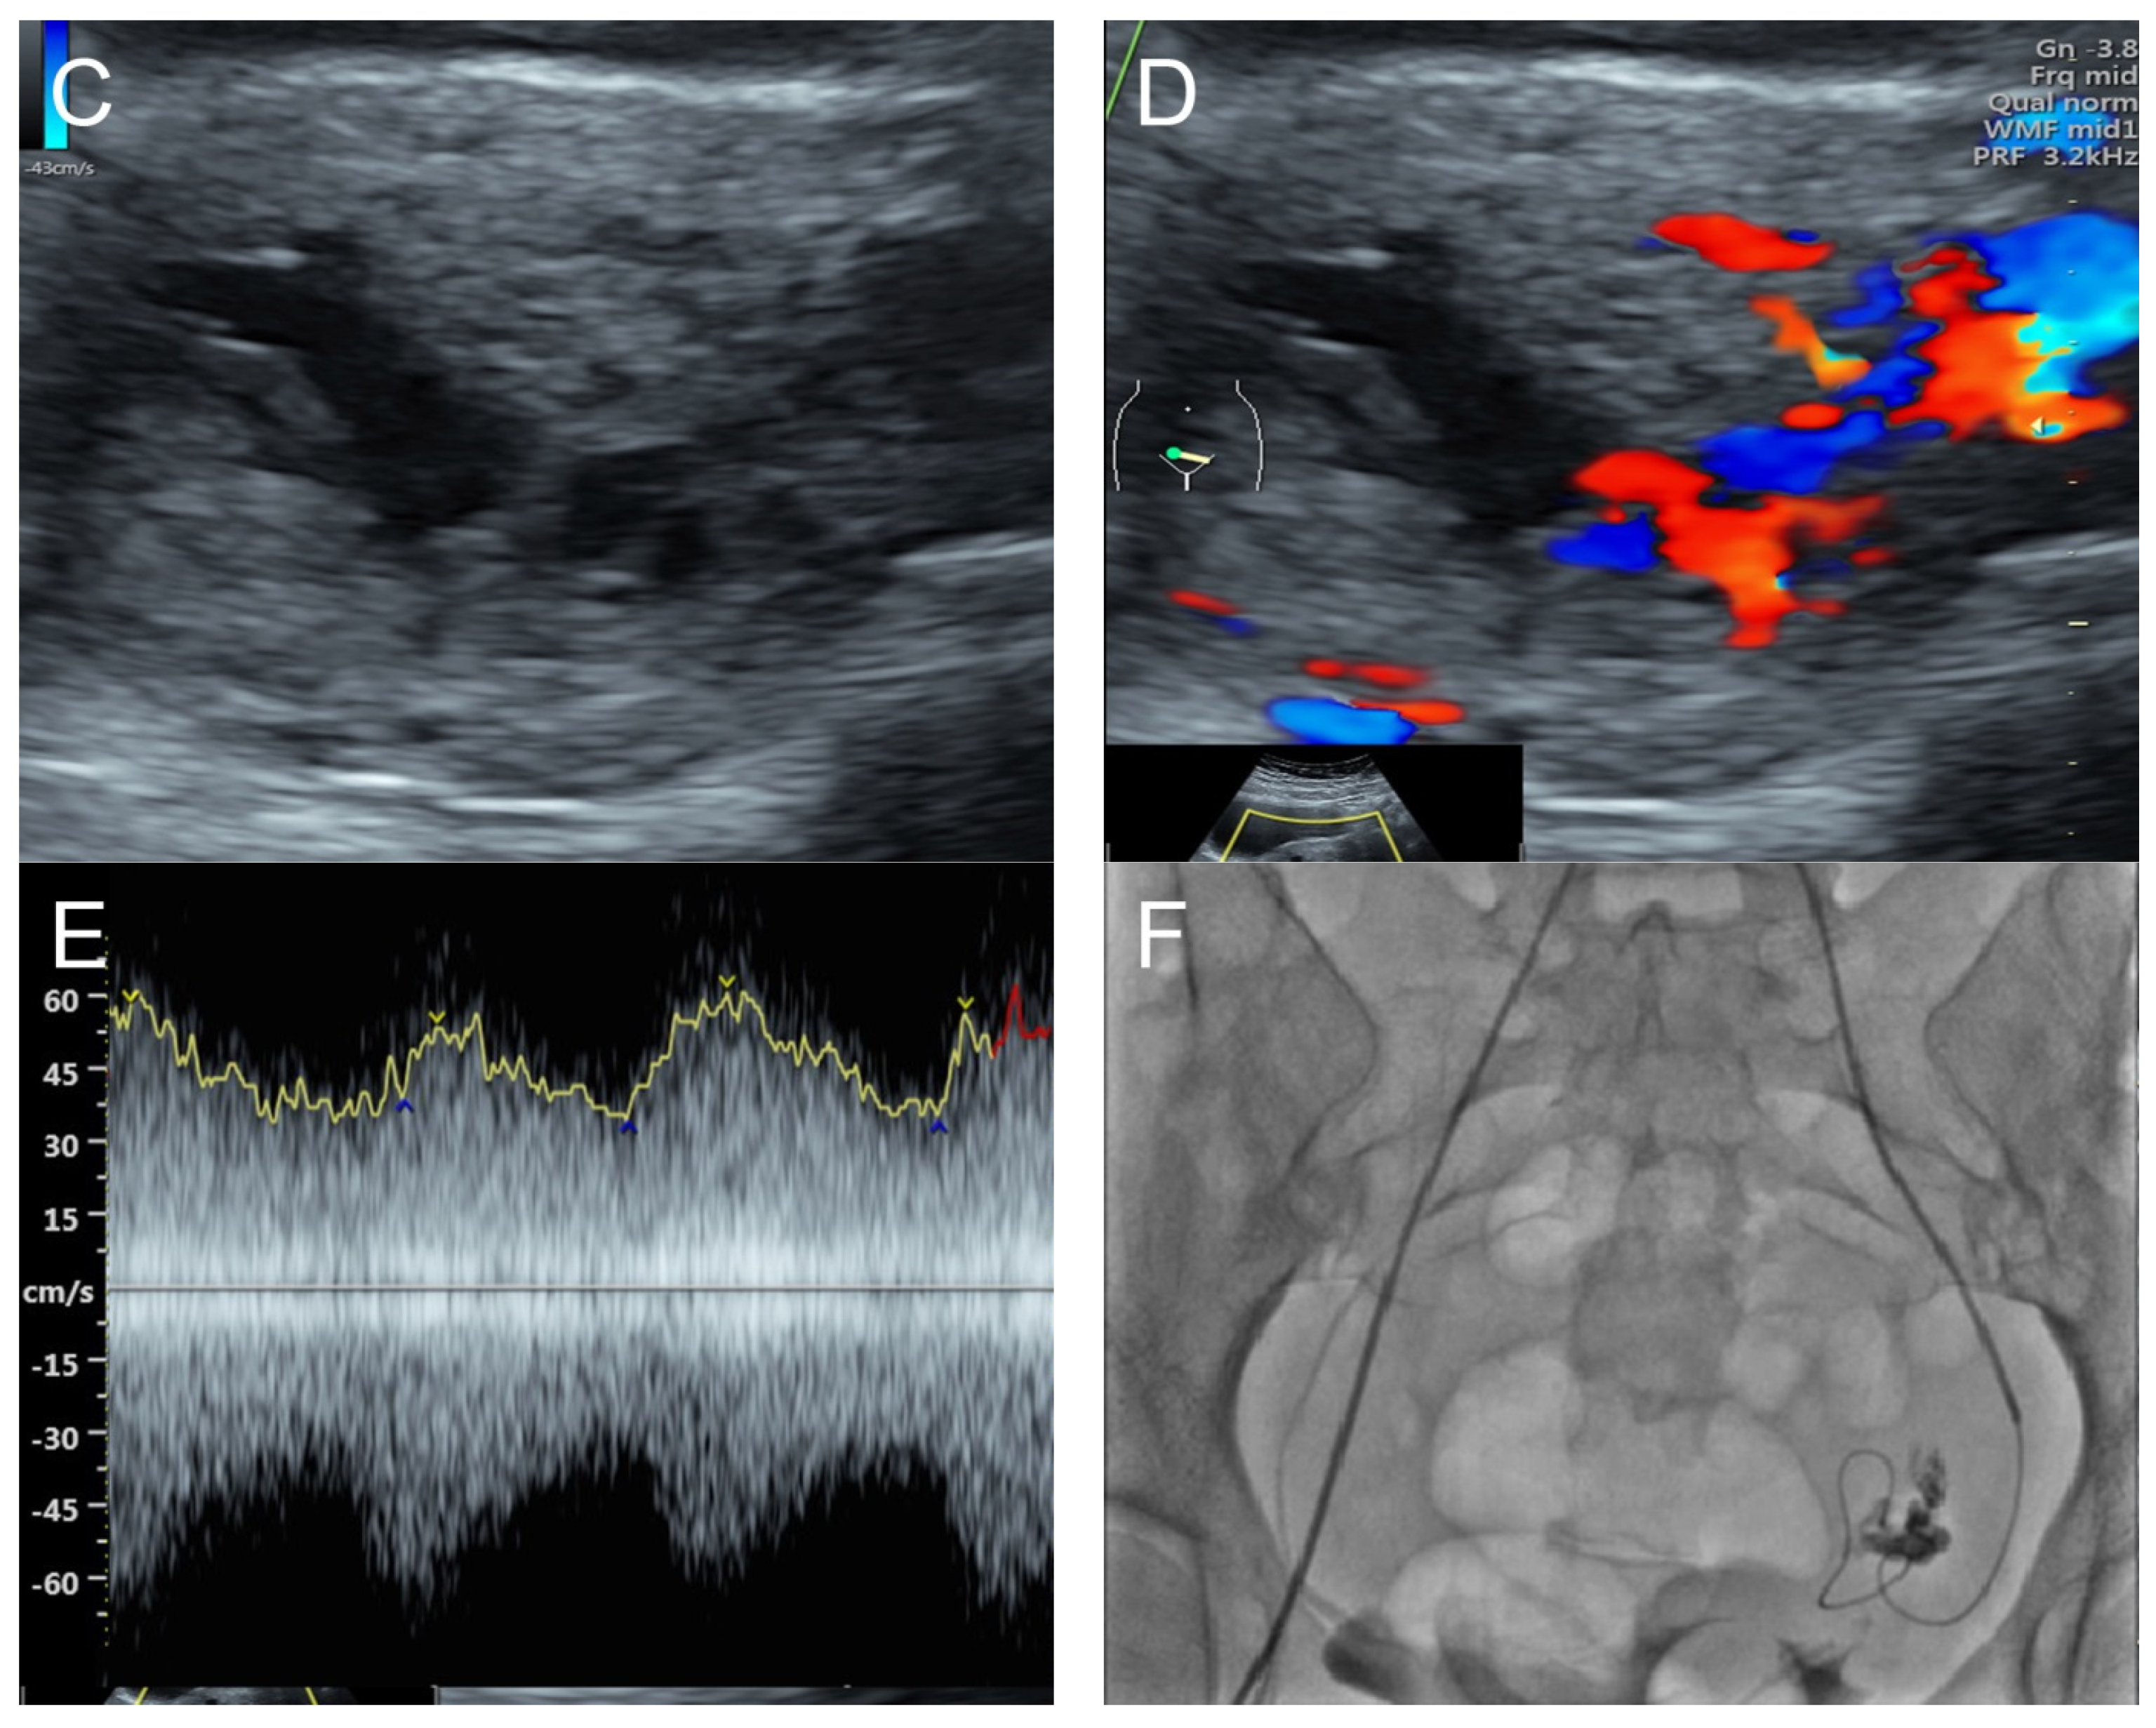

Figure 5.

(A,B) Transvaginal ultrasound: sagittal scans of the uterus showed several small anechoic/hypoechoic cysts, giving a spongy pattern and varying in size, throughout the myometrium; no other specific lesions of the uterus. The uterine cavity was lined with a thin endometrium and filled with anechoic fluid, probably lysed blood. (C) Color flow mapping showed hyper-vascularization in the cystic spaces, as seen in figure (A,B), throughout the myometrium and a multidirectional chaotic flow. The main differential diagnosis was adenomyosis or gestational trophoblastic disease. (D) Spectral Doppler showed a high peak systolic velocity (~70 cm/s) with a low resistance index of 0.2.